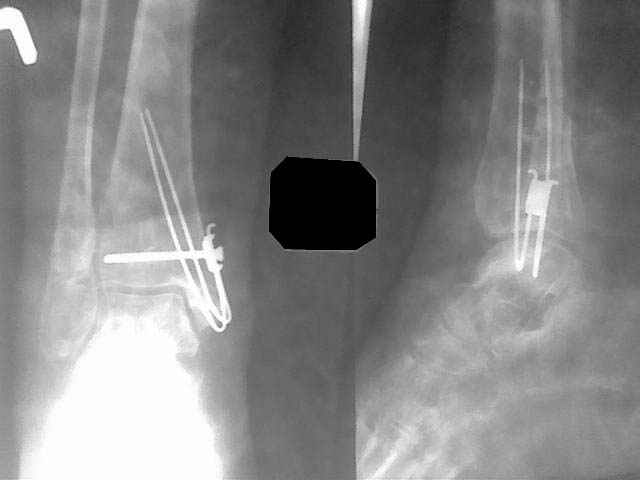

В данном случае - ложный сустав внутренней лодыжки на фоне оперативного лечения кортикальным винтом 3,5 и спицей. Часть внутренной лодыжки была лизирована. Проведена костная аутопластика. Результат налицо.